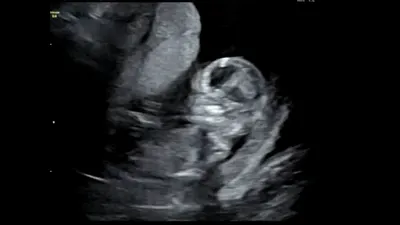

妊娠12週目の赤ちゃんの様子・エコー

12週頃の赤ちゃんは、それまで前かがみだった首や背骨が伸びて、徐々に骨が太く丈夫になっていきます。

エコーを当てると、腕や手の骨がはっきり見えるのもこの頃です。赤ちゃんによっては、ママのおなかの中を泳いだり、手足の曲げ伸ばしをしたりする様子も確認できますよ。

心臓や胃、腎臓などの内臓がほぼ完成し、それまで出ていた腸も体の中に収まって、徐々に機能しはじめます。

喉には声帯が、口には歯が生えはじめます。赤ちゃんは活発に動いていますが、胎動が感じられるのはもう少し先です。早い人は、赤ちゃんの性別がわかることがあります。